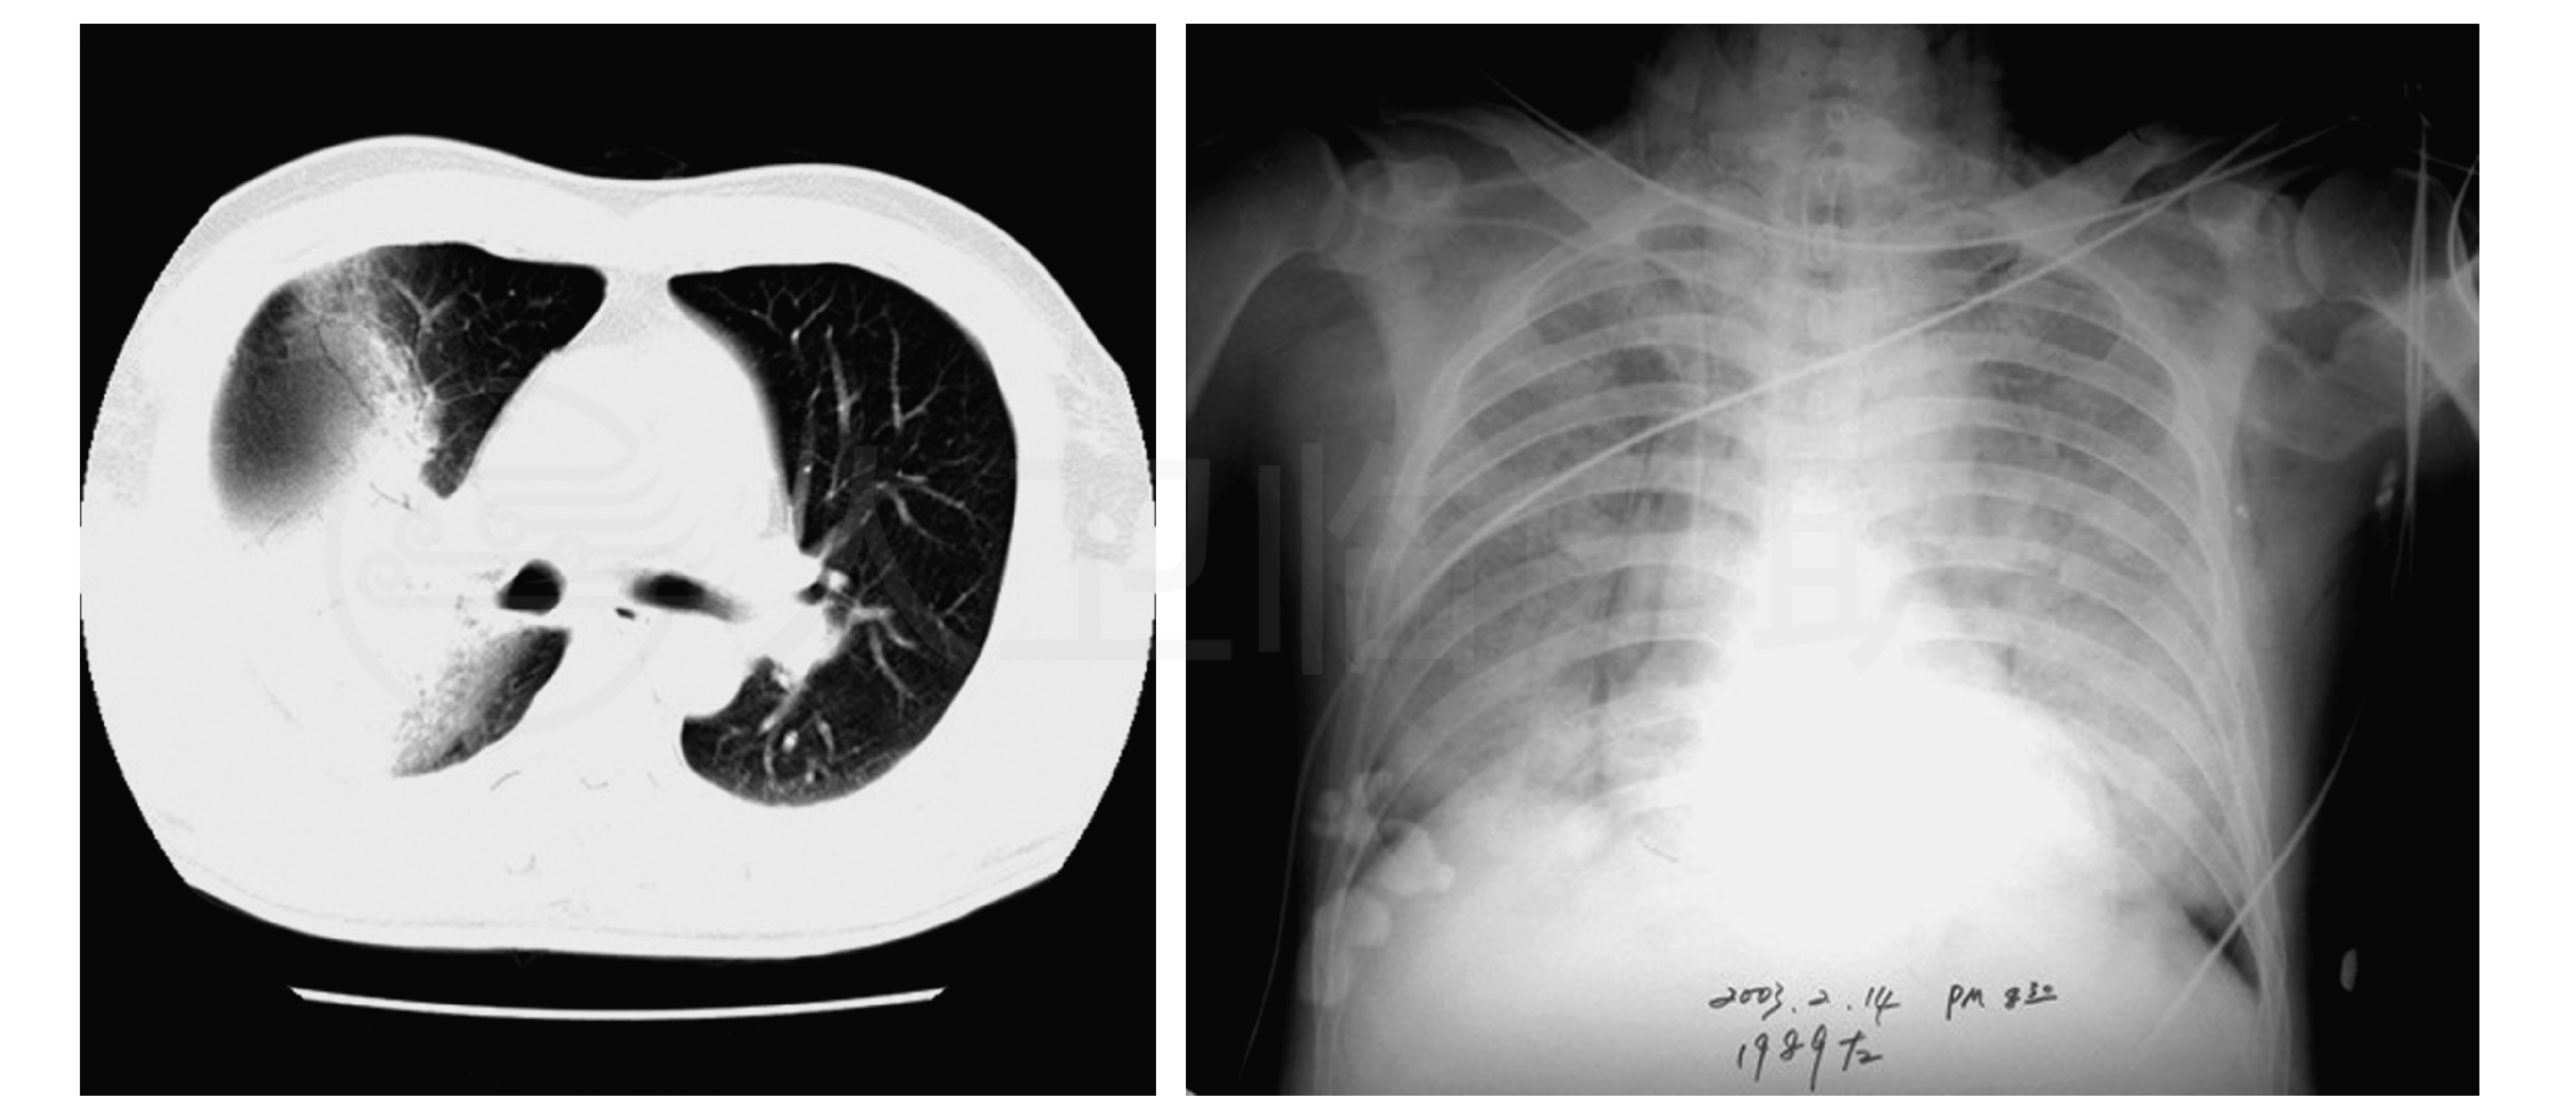

I have, like many in Hong Kong, survived the destructive SARS epidemic in 2003 (1). This Wuhan Pneumonia, (aka COVID-19) (2), simply looks too familiar, just larger in scale. Previously we have learned a few useful things to stay safe. Yet many in other parts of the world, even as technologically and medically advanced as US and Japan, appear to have been unprepared.

There was no medicine for this “severe acute respiratory syndrome” at the time, and this “SARS” virus spread with such ferocity that despite immediate mass awareness education, 1755 had been infected, 299 lives were taken. To many of the “recovered” persons, life has never been the same again. Their physical ability has been impaired by both the coronavirus and the unforgiving trial medicines used to save their lives.